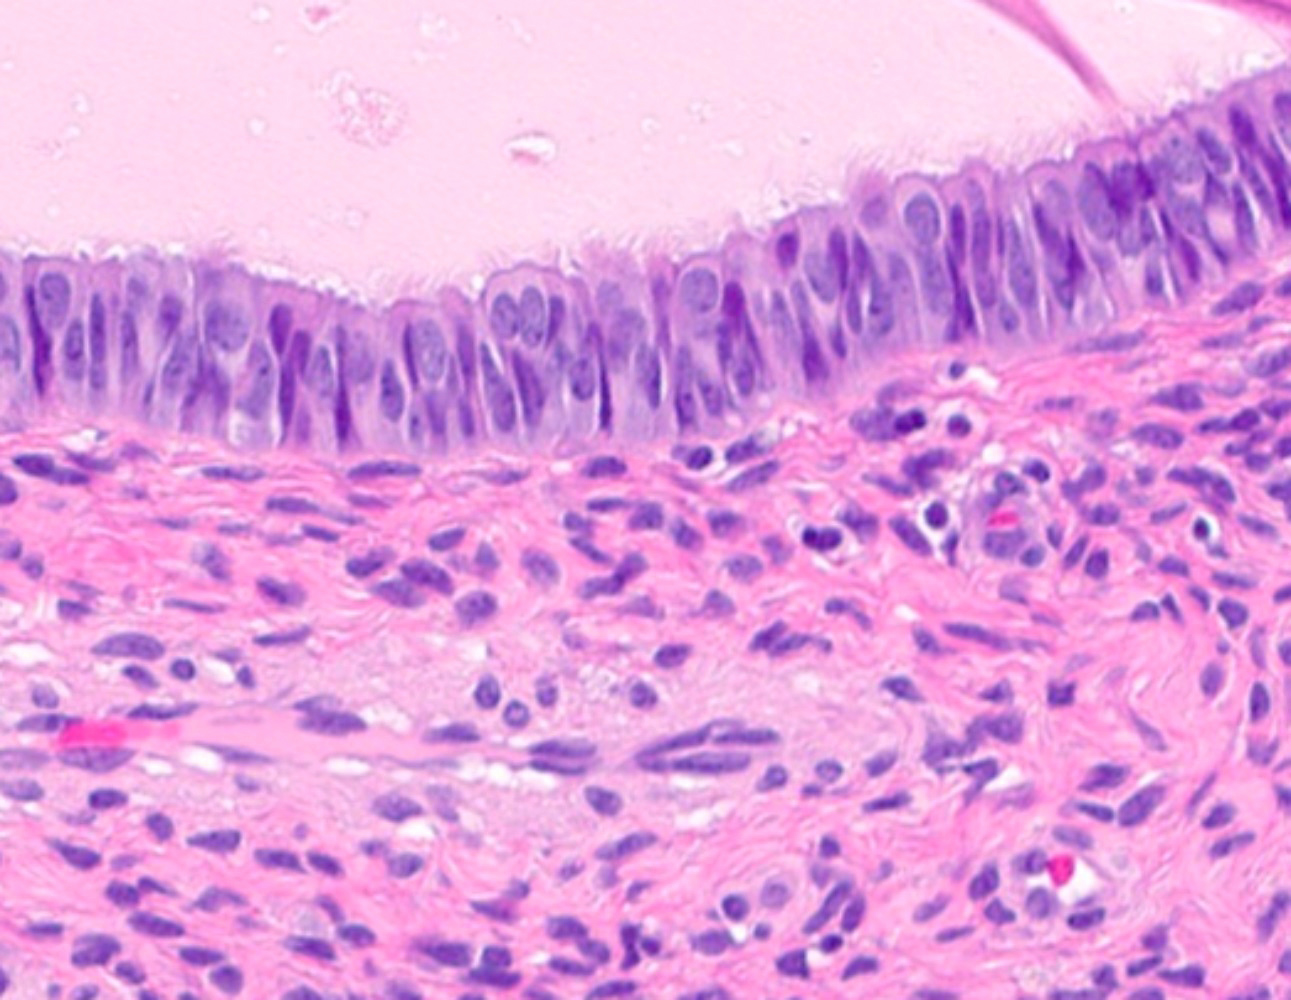

Microscopic (histologic) images

Contributed by Jessica L. Bentz, M.D.

- Tubal metaplasia (Mod Pathol 2011;24:1254):

- Resembling fallopian tube epithelium; pseudostratified with ciliated eosinophilic cells and clear round cells

- Eosinophilic metaplasia:

- Cuboidal to columnar cells with prominent eosinophilic cytoplasm, ranging from granular to dense

- Round nuclei with or without degenerative atypia